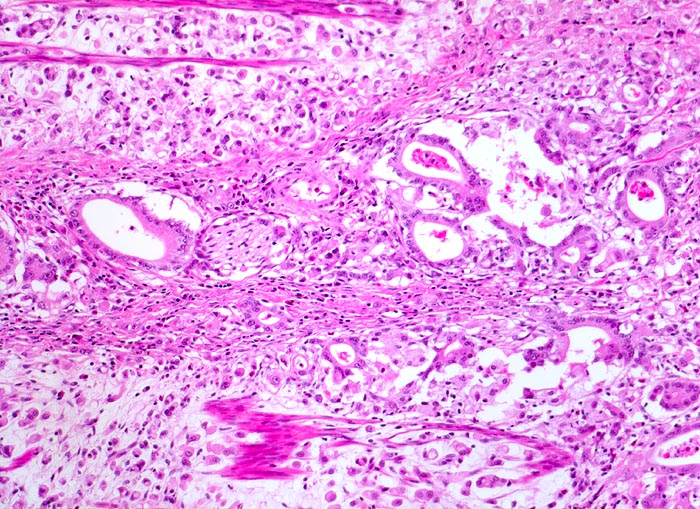

AP/ Adenokarzinom des Magens

Adenokarzinom des Magens

Die ersten beiden Typen entsprechen histologisch meist einem intestinalen Typ nach Lauren (> 1342). Diese Tumoren sind scharf begrenzt, bilden tubuläre oder papilläre Strukturen wie die Dickdarmkarzinome, sind meist assoziiert mit bekannten umweltbedingten Risikofaktoren und haben eine bessere Prognose.

Beim diffusen Typ nach Lauren infiltrieren Einzelzellen oder Zellstränge, meist mit Siegelringzellanteilen diffus die Magenwand. Eine Drüsenbildung ist nicht erkennbar. Dieser Tumortyp tritt bei relativ jungen Patienten auf und ist mit genetischen Faktoren assoziiert (positive Familienanamnese). Wegen des diffus infiltrativen Wachstums ohne makroskopisch sicher erkennbare Grenze müssen diese Tumoren mit einem grösseren Sicherheitsabstand operiert werden. Siegelringkarzinome machen rund 20% aller Magenkarzinome aus.

Adenokarzinome können tubuläre, papilläre, muzinöse, siegelringzellige und undifferenzierte Anteile aufweisen, wobei die beiden letzteren besonders aggressive Tumoren darstellen.

Morphologische Merkmale:

• Gewebsfragment aus gastroösophagealem Übergang.

• Das unscharf begrenzte Karzinom breitet sich diffus in der gesamten Magenwand und in der Ösophaguswand aus bis in des periösophageale und subseröse Fettgewebe.

• Ösophagus mit intaktem plattenepithelialem Schleimhautüberzug.

• Ein Grossteil des Tumorinfiltrats besteht aus einzeln oder in kleinen Gruppen liegenden Zellen mit intrazytoplasmatischen Schleimvakuolen, die teilweise den Kern verdrängen (Siegelringzellen): diffuser Typ des Magenkarzinoms nach Lauren.

• Nur vereinzelt Drüsenbildung.

• Lymphgefässeinbrüche.